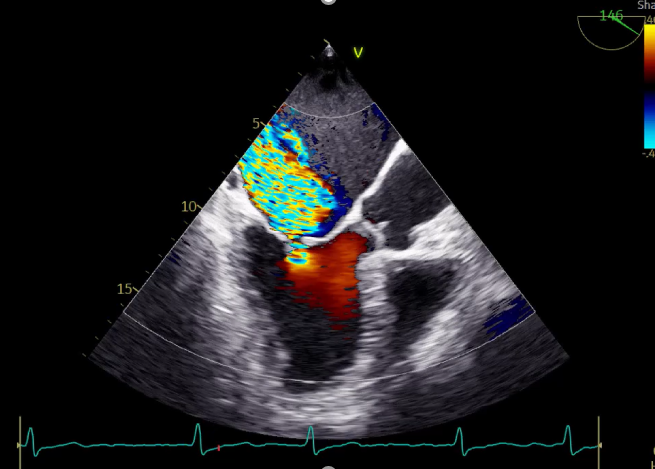

LVOT-color:MR(重度),返流面积11.3cm2

肺静脉血流频谱呈收缩期反向

3D-color MV view:血流主要来源于2、3区

Qlab软件勾画估测瓣口面积约:6.16cm2

TEE LVOT切面返流量评估

TEE 4-Ch view返流量评估